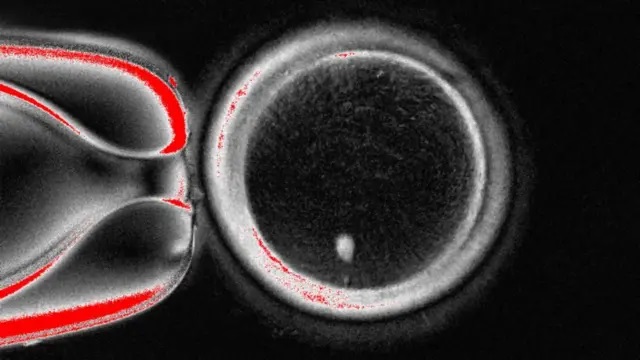

รายงานการศึกษาฉบับนี้ซึ่งถูกตีพิมพ์ในวารสารเนเจอร์ คอมมูนิเคชันส์ (Nature Communications)แสดงให้เห็นการสร้างไข่ที่มีศักยภาพในการผลิตตัวอ่อน 82 ใบ ซึ่งทั้งหมดถูกผสมด้วยอสุจิแล้ว และไข่บางใบก็พัฒนาไปถึงระยะแรกของการพัฒนาตัวอ่อน ทว่ายังไม่มีไข่ใบใดที่พัฒนามาเกินกว่าระยะเวลา 6 วัน